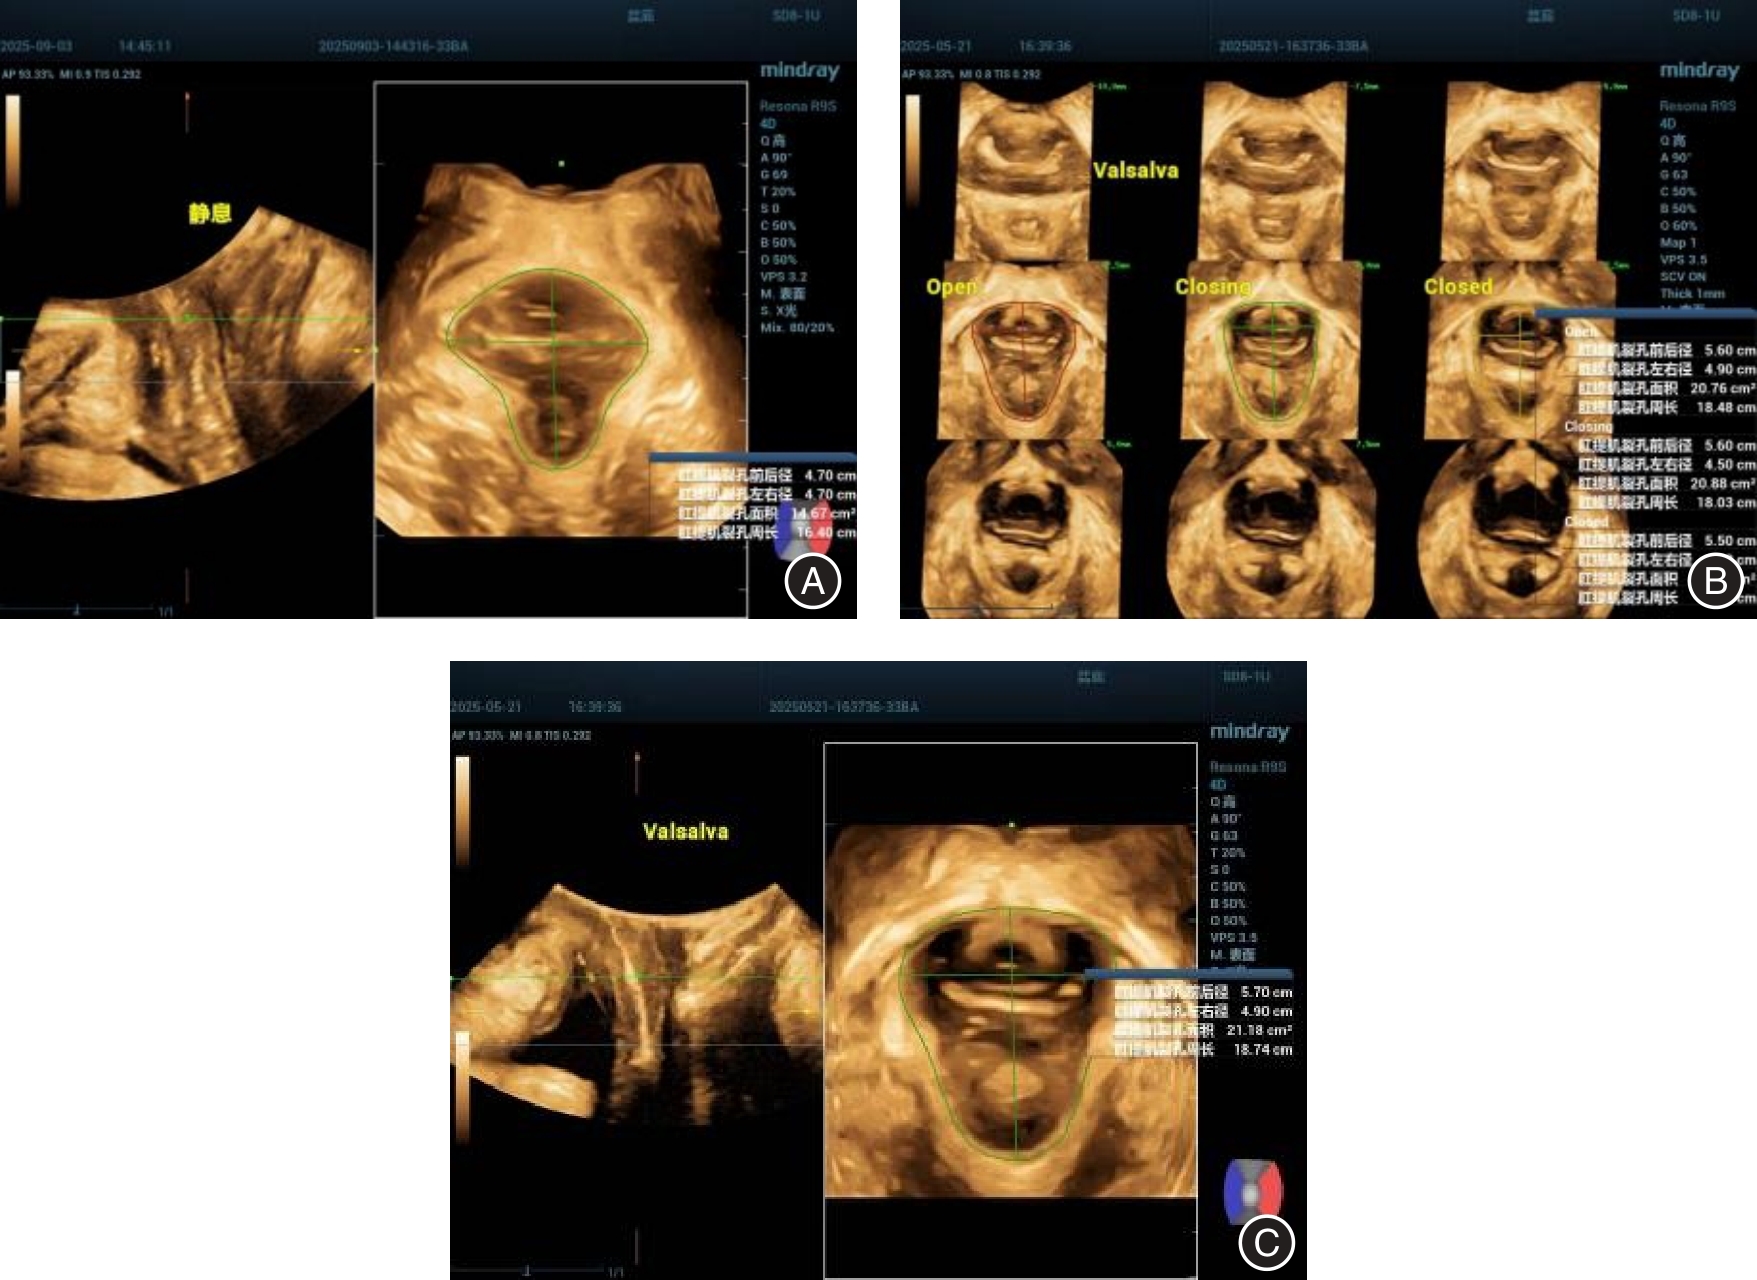

潘雪葵,朱玲,蔡婷婷,等. 肛提肌裂孔面积联合剪切波弹性成像对产后盆腔器官脱垂的评估价值[J]. 中国超声医学杂志, 2025, 41(6): 694-698.

河南省超声医学质量控制专家委员会, 王睿丽, 朱兆领, 等.盆底超声临床实用规范化检查专家共识(2022版)[J]. 中国医学影像学杂志, 2023, 31(2): 97-99.